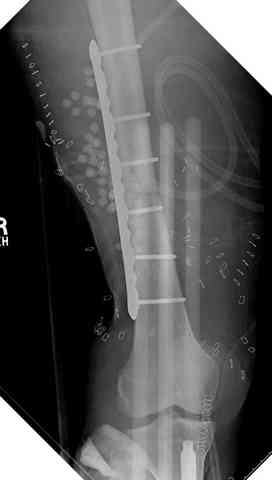

Огнестрельный дефект костей и передней группы мышц, поступил с юнилатеральным аппаратом, стабильность плохая, из раны обильное гнойное

отделяемое. #1;#2. Стержневой апп. снят, наложен апп. Илизарова, дренажно-ирригационная система промывки раны. #3; #4. После стихания инфекции,

аппаратом постепенно создана рекурвация для сближения контактов мышц (сухожилий) передней группы голени. #5;#6. Наложен шов на сухожлилия М.

Tibialis anterior и M extensor digitorum L. Одновременно компактотомия костей голени в В/3 для замешение дефекта костей. #7;#8. Постепенно

исправлена ось и возмещен дефект. В результате восстановление тыльной флекcии стопы и функции конечности. #9;#10;#11

здесь случай с политравмой, перелом зафиксирован наружным фиксатором, после третьей irrigation&debridment фиксация бедра пластиной с последующей кожной пластикой.